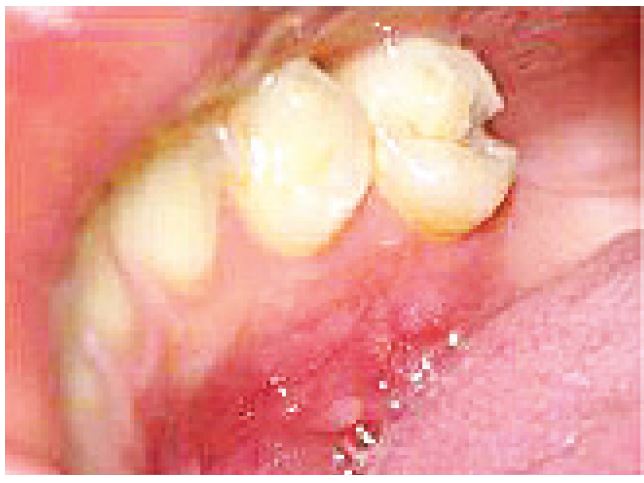

The patient returned to the dental service after two months, with the area fully healed (Figure 5).